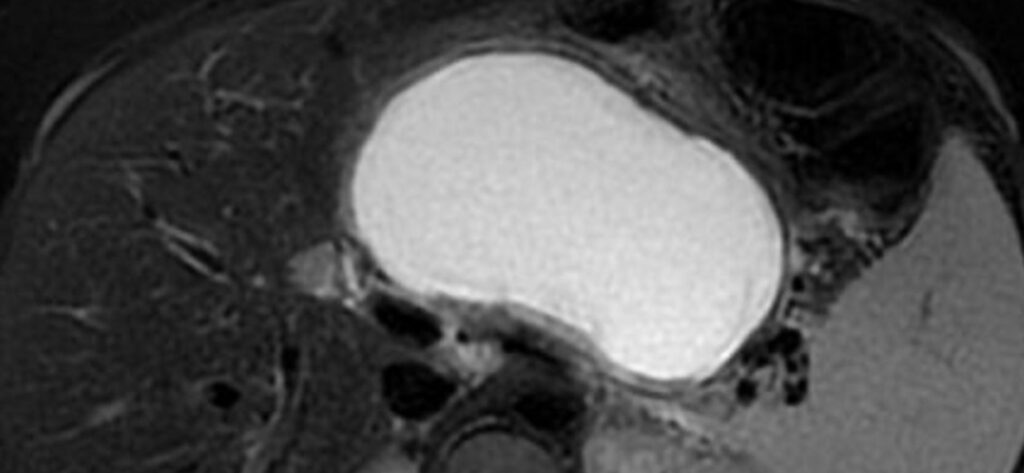

Lesioni cistiche del pancreas

Epidemiologia Le lesioni cistiche del pancreas sono sempre più diagnosticate grazie all’uso diffuso di tecniche di imaging avanzate come la TC (Tomografia Computerizzata) e la